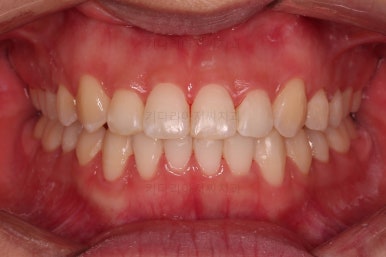

치료가 1년만에 종료가 되었네요.

치아가 가지런해졌고, 교합이 잘 맞는 모습이에요.

부산교정 전후사진을 비교해 볼게요.

치열의 모습이 좋아졌고, 웃을 때 보이는 치열이 가지런해서 미소도 훨씬 예뻐졌네요.

옆라인이라던지 입을 다물었을 때의 느낌은 원래도 좋으셨기 때문에 거의 그대로 유지가 되었고요.